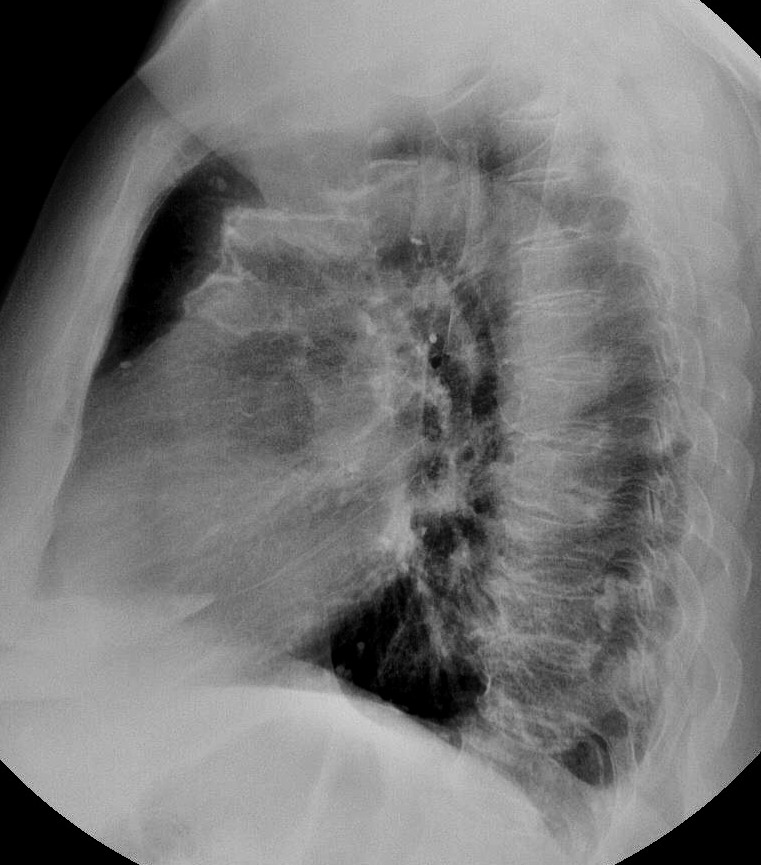

Изолированые петрификаты - в верхних долях; масивные обызествления ПЛЕВРЫ, просто такое обызествление имеет БОЛЬШУЮ толщину, чем обычные листки ...потому и как бы НАПЛЫВАЕТ на легкие. Такое мое мнение.

Эта рентгеновская картина характерна для обызвествления костальной плевры.

я согласен, но почему на томо изменения начинаются в легочной ткани, на тех же уровнях ,что некоторые и кальцинаты?